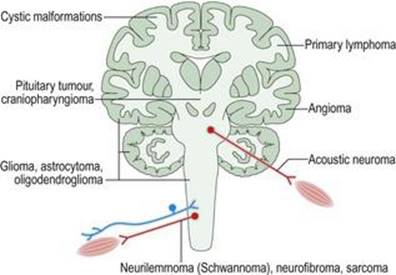

نئوپلازی به رشد بیش از حد و کنترل نشده بافتها اشاره دارد که یک تومور خوش خیم یا بدخیم را تشکیل میدهند. نئوپلاسمهای اولیه در خود بافتهای عصبی عضلانی ایجاد میشوند (شکل ۱.۳۶). نئوپلاسمهای ثانویه در گردش خون از سایر مکانهای اندام اولیه (مانند ریه یا سینه) پخش میشوند. به ندرت، تومورها در مکانهای دور توسط مکانیسمهای هومورال یا ایمنی به سیستم عصبی آسیب میرسانند و اختلالات ناشی از آن سندرمهای غیر متاستاتیک یا پارانئوپلاستیک نامیده میشوند (شکل ۱.۳۷).

شکل ۱.۳۶ نئوپلازی سیستم عصبی عضلانی.

شکل ۱.۳۶ نئوپلازی سیستم عصبی عضلانی.

شکل ۱.۳۷ سندرمهای پارانئوپلاستیک سیستم عصبی عضلانی.

شکل ۱.۳۷ سندرمهای پارانئوپلاستیک سیستم عصبی عضلانی.